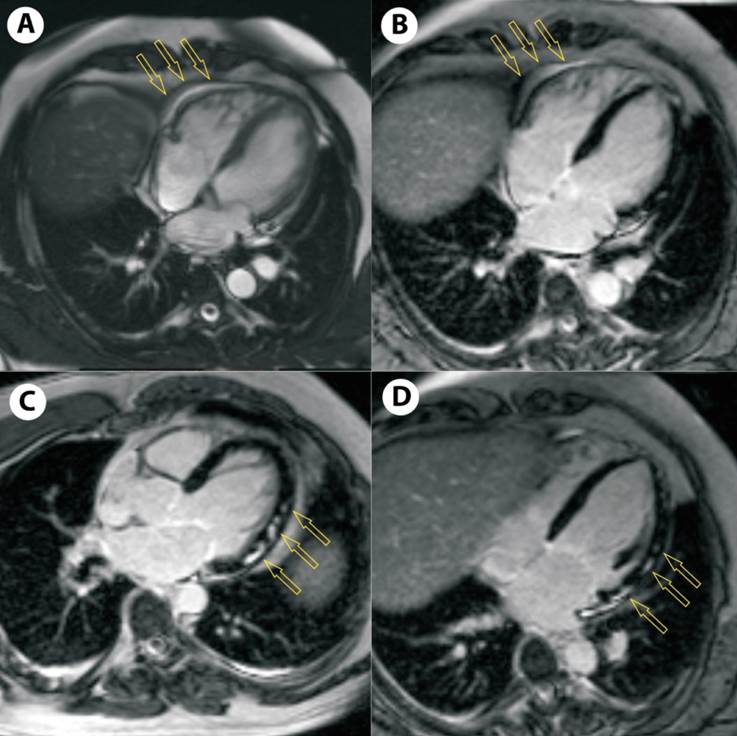

En la RMC con contraste de gadolinio se observa hipocinesia global discreta del ventrículo izquierdo, fracción de eyección de 54%, leve derrame pericárdico, presencia de edema y realce tardío con patrón parcheado subepicárdico e intramiocárdico en pared lateral (figura 2).

En los casos sospechosos de miopericarditis, se recomienda realizar angiografía coronaria (según la presentación clínica y la evaluación de factores de riesgo) para descartar un síndrome coronario agudo. La RMC está recomendada para confirmar afección miocárdica y descartar la necrosis miocárdica isquémica en ausencia de enfermedad coronaria significativa. El derrame pericárdico y el realce tardío de gadolinio con patrón parcheado subepicárdico e intramiocárdico junto con edema miocárdico en diferentes territorios vasculares es indicativo de miopericarditis(3,6).